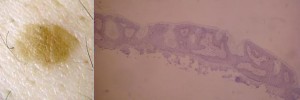

Smooth appearing young SK with a histological diagnosis in the Reticulo-acanthosic type (RA). This corresponds to a thin stratum corneum.

Clinically smooth lesions were of the reticulate and/or acanthotic type and keratotic lesions were of the acanthohyperkeratotic type. If we consider that SK have pulsed stimulations to hyperproliferate or to accumulate, we can admit that all SKs evolve from paucicellular smooth lesions of the reticulate-acanthotic type to pluricellular thickened SK of the acantho-hyperkeratotic type. These paucicellular smooth lesions arise from macular SK, considered by some a solar lentigo. No clonal SKs were detected in our study and their probable rarity does not enable us to hypothesize a relationship between the clinical and histological picture of this subtype.